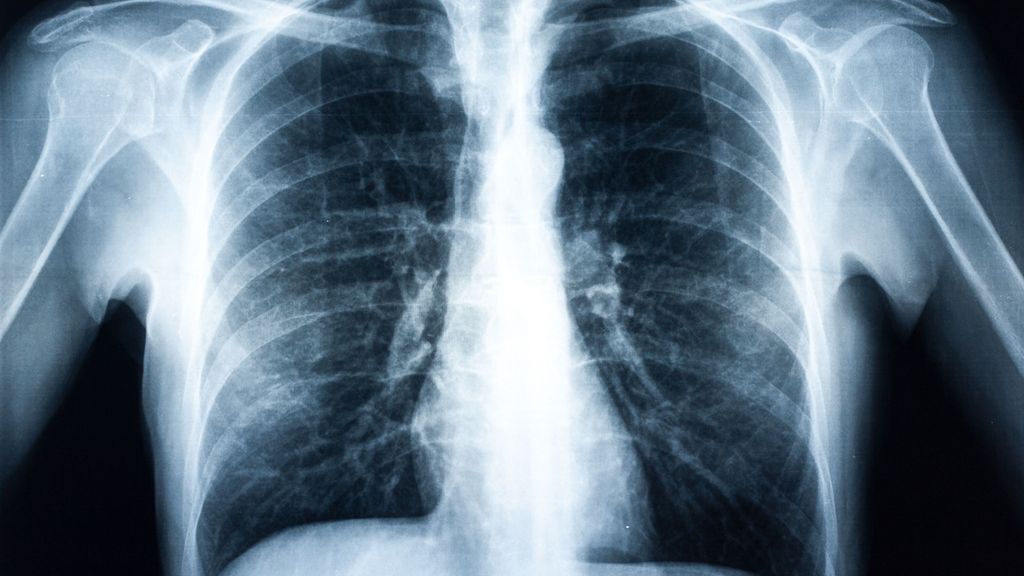

De nombreuses personnes atteintes de BPCO et/ou d’asthme n’ont jamais été diagnostiquées et ne sont donc pas traitées. Plusieurs études publiées ces derniers mois se penchent sur ce ...

Plusieurs principes actifs sont actuellement en cours de développement dans le traitement de la fibrose pulmonaire idiopathique (FPI) et de la fibrose pulmonaire progressive (FPP), en ...